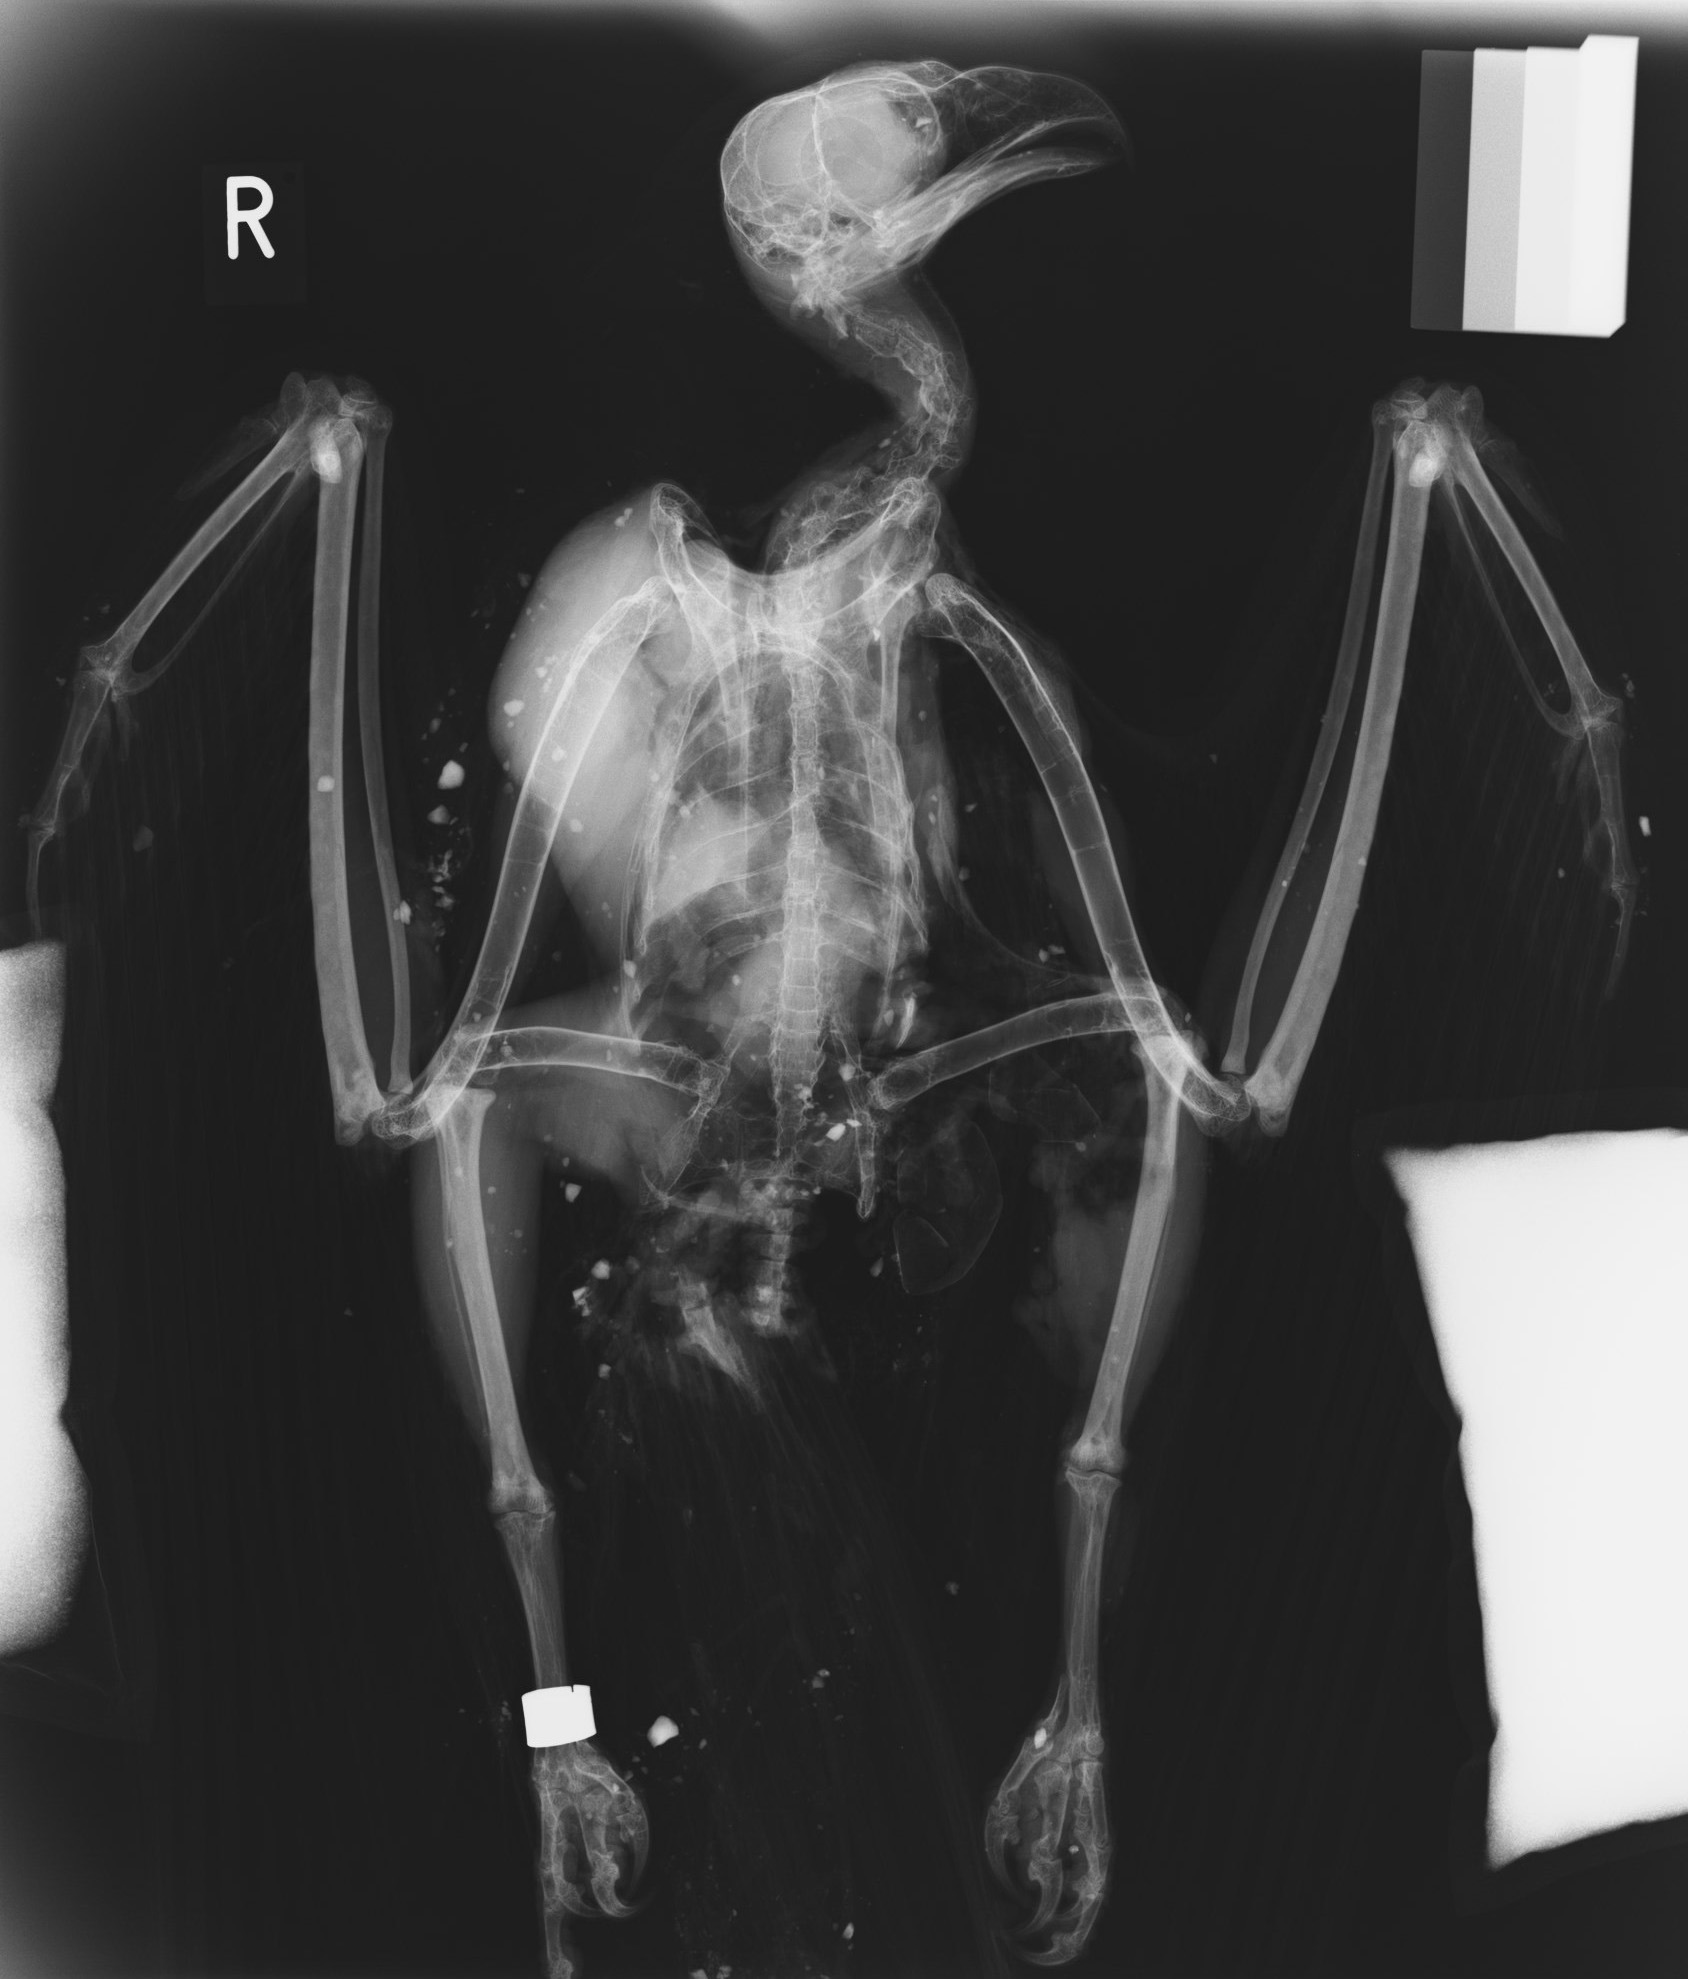

Wild Animal Health will carry out post-mortem examinations of free-living, and captive, wild animals to reveal the diagnoses which have been associated with death. All species of mammal, bird, reptile, amphibian or invertebrate will be accepted for investigation. Each case is assessed based on gross pathological findings and further diagnostic tests may include bacteriology, mycology, virology, histopathology and toxicology. These investigations aim to provide a thorough understanding of the underlying causes and contributing factors in the wild animal’s death.